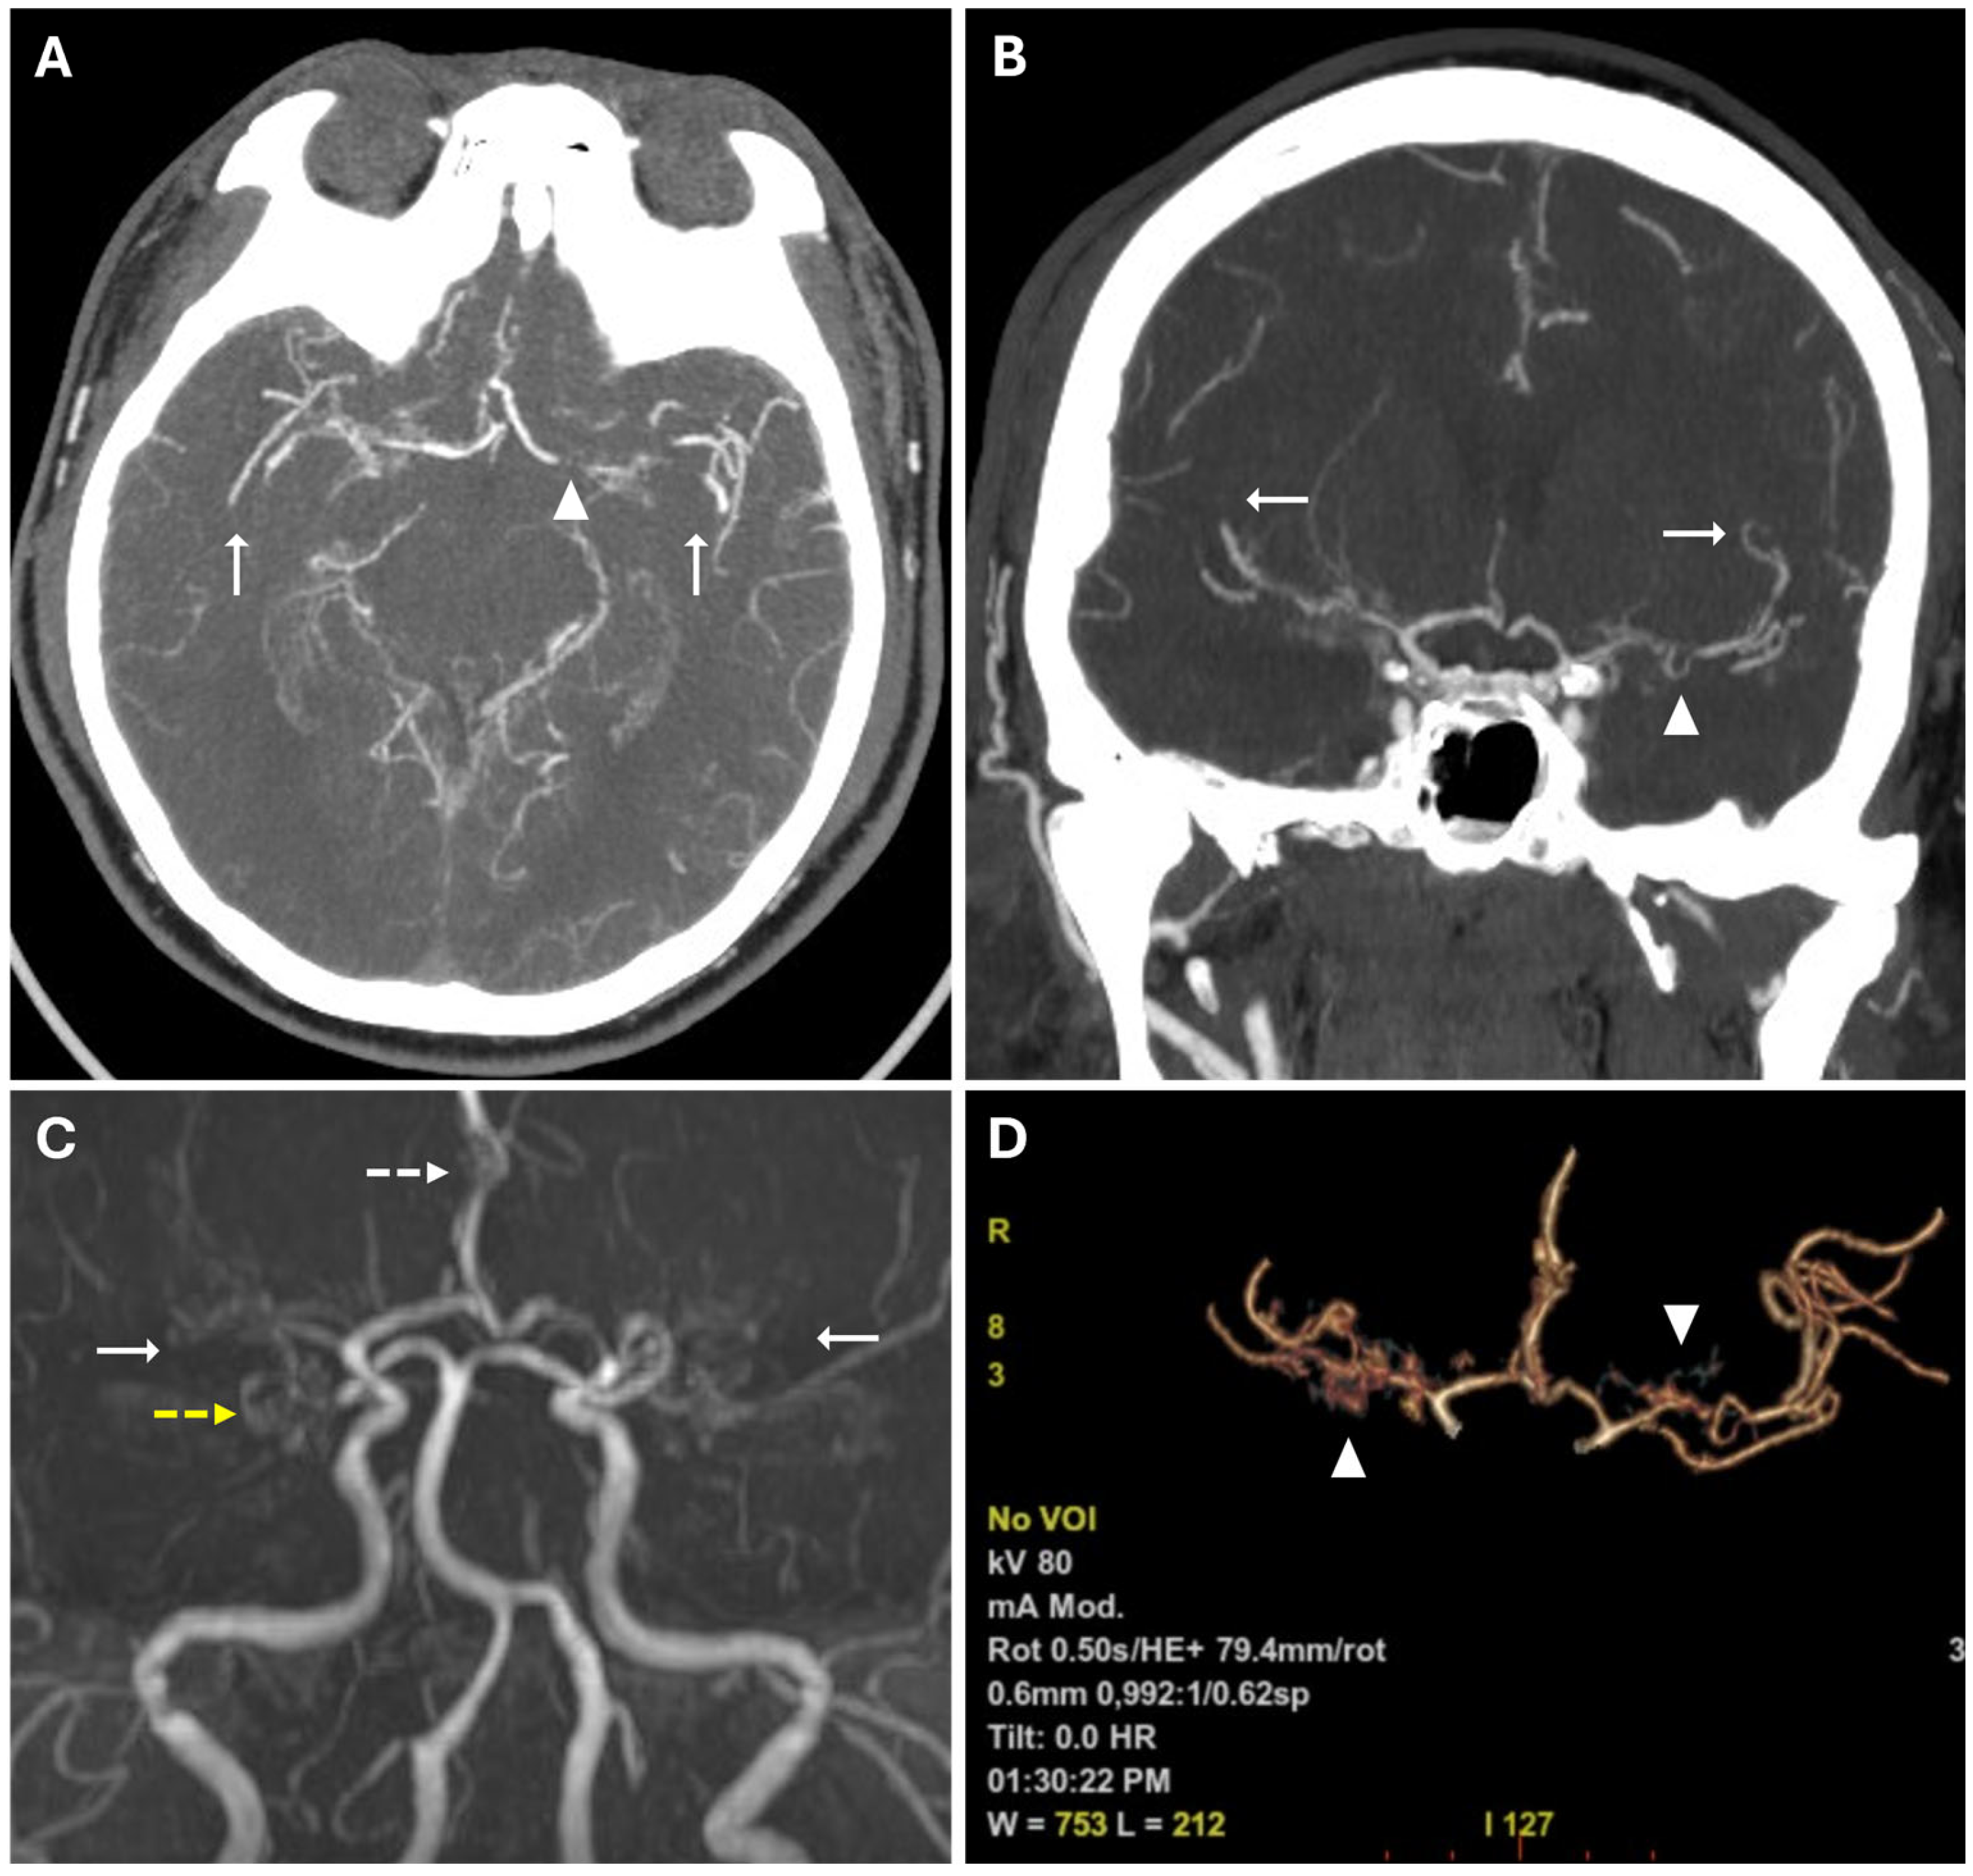

To confirm the diagnosis and to assess disease staging, DSA was performed using a six-vessel approach (ICAs, ECAs, and vertebral arteries), revealing significant stenosis of both M1 segments of the middle cerebral arteries, more prominent on the right, associated with mild progressive caliber reduction in supraclinoid internal carotid arteries (“champagne bottle neck” sign) and abnormal moyamoya vessels within basal ganglia and thalami, represented by hypertrophic lenticulostriate and thalamoperforating arteries (“puff of smoke” sign) (Figure 5).

Figure 5. Digital subtraction angiography of MMD. Anteroposterior (A) and lateral views (B) of the right internal carotid artery injection show extensive and severe stenosis of the M1 tract of MCA and progressive caliber reduction in supraclinoid segment of the ICAs (“champagne bottle neck” sign, black arrows); notice the wide perforator network represented by lenticulostriate and thalamic arteries, resembling a “puff of smoke” (white arrowheads). Anteroposterior (C) and lateral views (D) of the left internal carotid artery injection demonstrate mild stenosis of the supraclinoid segment of the ICA (black arrow in (D)), of the distal portion of the M1 segment of MCA and multiple focal stenoses involving the ACA and M2; moyamoya vessels are less evident than on the right side. Anteroposterior (E) and lateral views (F) of posterior circulation injection show collateral pathways through posterior lenticulostriate arteries at the basal ganglia level, and leptomeningeal collaterals are more prominent in the right temporal lobe and left temporoparietal region (white arrows).

Multiple and focal stenoses were detected at the origins of M2 branches and the proximal A1 segment of the right ACA, also with the involvement of P1–P2 segments of both PCAs. The blood supply to the cerebral hemispheres was allowed by collateral circulation through leptomeningeal anastomoses from posterior circulation and anterior cerebral arteries, and through choroidal and perforator arteries arising from M1 and P1. Collateral supply through the external carotid arteries was absent. According to DSA findings and excluding secondary causes of MMS, the patient was classified as Suzuki stage III of idiopathic MMD.

Bilateral and, especially, unilateral MMD need confirmation with angiography, also allowing treatment planning. DSA should be performed using a five-vessel or six-vessel approach, including imaging of both external and internal carotid arteries, and one or both vertebral arteries [3,9]. In the context of preoperative imaging, the assessment of the external carotid arteries is paramount for the identification of preexisting collateral vessels, especially at the level of the orbit through the ophthalmic artery and the posterior and anterior ethmoidal arteries; this is of critical importance to avoid their disruption during surgical intervention [24]. Angiography identifies narrowing of proximal and extracranial segments of ICA (“bottle neck” sign), and abnormal proliferation of lenticulostriate and thalamoperforator vessels, giving the characteristic “puff of smoke” appearance (Figure 5). Furthermore, aneurysms and any arteriovenous malformations associated with moyamoya are most effectively detected through conventional angiography rather than CT or MR [3]. In 2021, the revised version of the “Diagnostic Criteria for Moyamoya Disease” delineated the following diagnostic angiographic findings of MMD [11]: